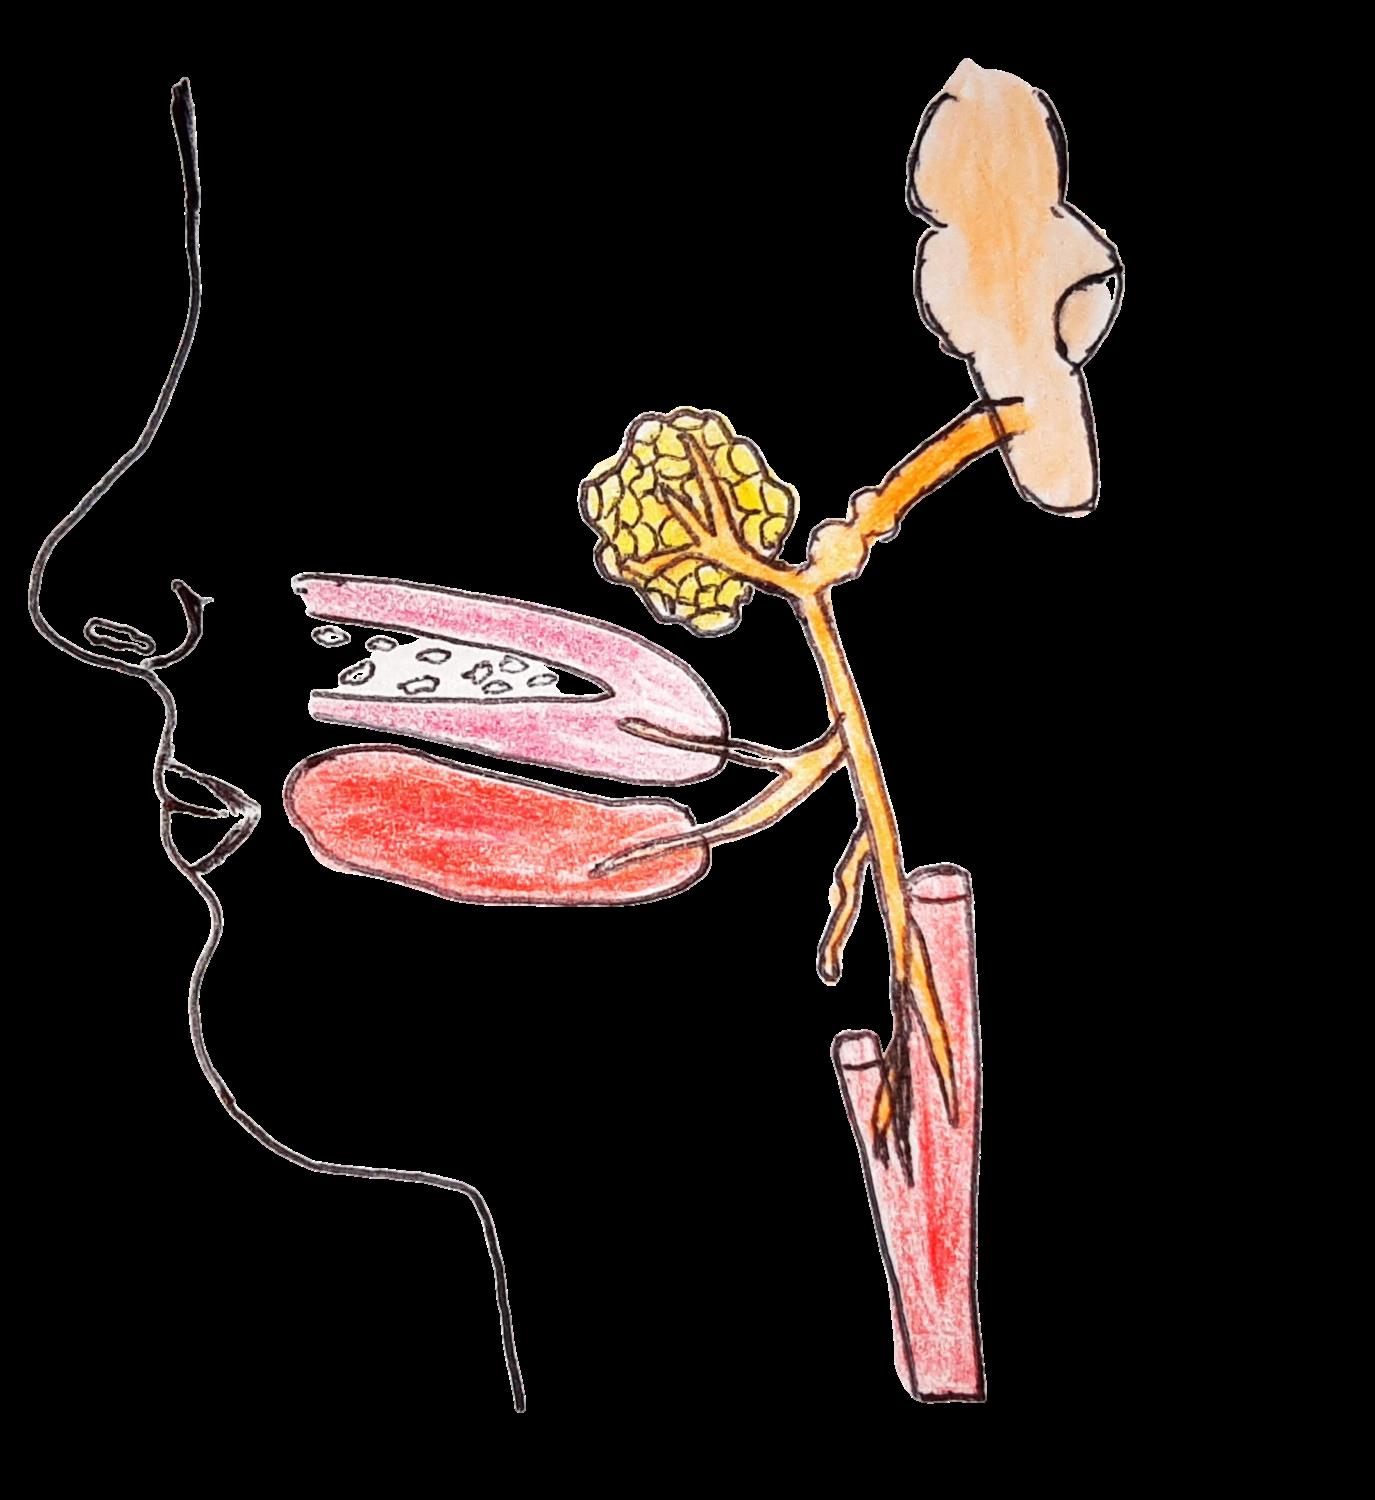

NERVIO GLOSOFARÍNGEO (IX PAR)

Glándula salival parótida

CARACTERÍSTICAS:

Médula oblongada NERVIO GLOSOFARÍNGE O

Es un nervio mixto, tiene una función motora y sensorial Es el nervio del reflejo nauseoso y la deglución Encargado de modular los tiempos de la deglución, función compartida con los nervios facial y vago

Ramas linguales

Arteria carótida común